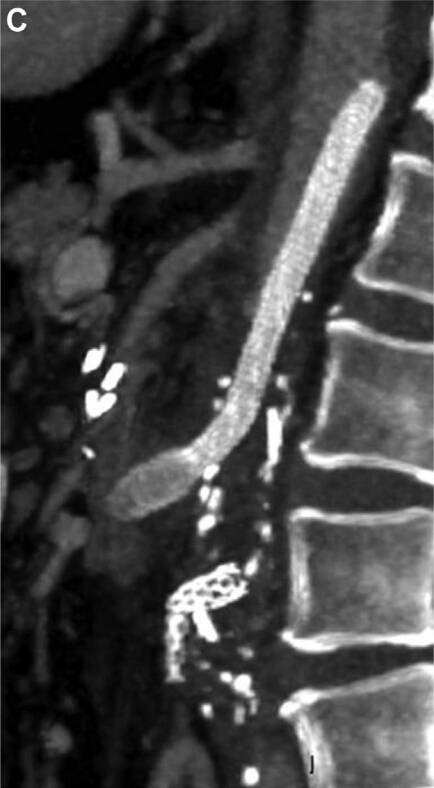

CT 血管造影显示:股动脉至下腹主动脉整段闭塞,腹腔干和肠系膜下动脉闭塞(曾置入支架),肠系膜上动脉(SMA)严重狭窄(图 A)。

图 A. CT 血管造影